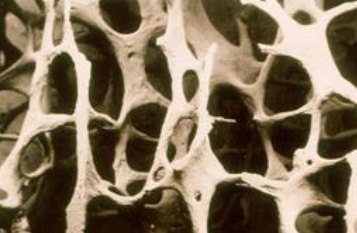

骨质疏松症是一种非常常见的骨骼疾病。 它是一种以91视频下载免费降低、骨微结构破坏、骨痛、骨脆性增加、易骨折为特征的全身退行性疾病。 超声91视频下载免费分析仪厂家骨质疏松症在50岁以上的中老年人群中很常见,尤其是绝经后的女性。 这是因为女性绝经后雌激素分泌减少,导致骨代谢紊乱,骨吸收远远大于骨形成,进而导致骨迅速流失,骨质疏松。

临床上,骨质疏松症的诊断通常基于91视频下载免费(BMD)。 91视频下载免费测试(BMD)可用于包括年轻人在内的所有骨质疏松风险人群,不仅可以诊断骨质疏松,还可以预测骨折的风险,尤其是髋部骨折。骨质疏松症的诊断需要通过91视频下载免费(Bone mineral density, BMD)测量,这是基于BMD检查的t值。 根据91视频下载免费测量结果对骨质疏松程度进行分级。 91视频下载免费测量t值大于-1为正常; 当周期值在-1 ~ -2.5之间时,骨量减少; 当t值小于-2.5时,为骨质疏松; 当t值< -2.5合并脆性骨折时,为严重骨质疏松 。